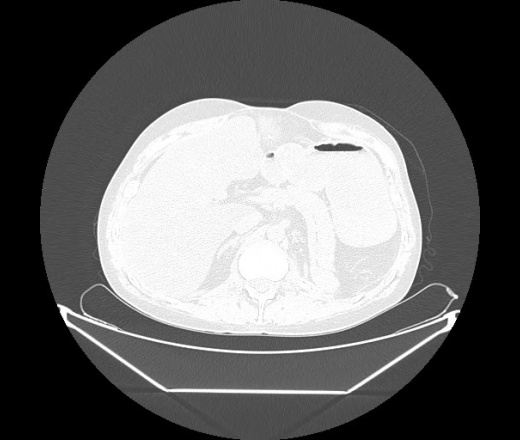

М. 1984 г.р.  Лихорадка 39, кашель , одышка.. и надоевший всем вопрос- "типично ли для ковид?" ( в настоящее время на него обязательно нужно дать ответ в своем протоколе)

На мой взгляд нетипично для ковид: много центрально-расположенных поражений, лобарное поражение нижней доли слева. 50/50

Не типичая картина для ковид.

КТ-признаки двусторонней бактериальной пневмонии.

Все верно, здесь абсолютно нетипичная картина, несмотря на матовое стекло с ретикулярными изменениями, но почему-то  посчитали иначе. Кстати,  "малыша" не заметили)?